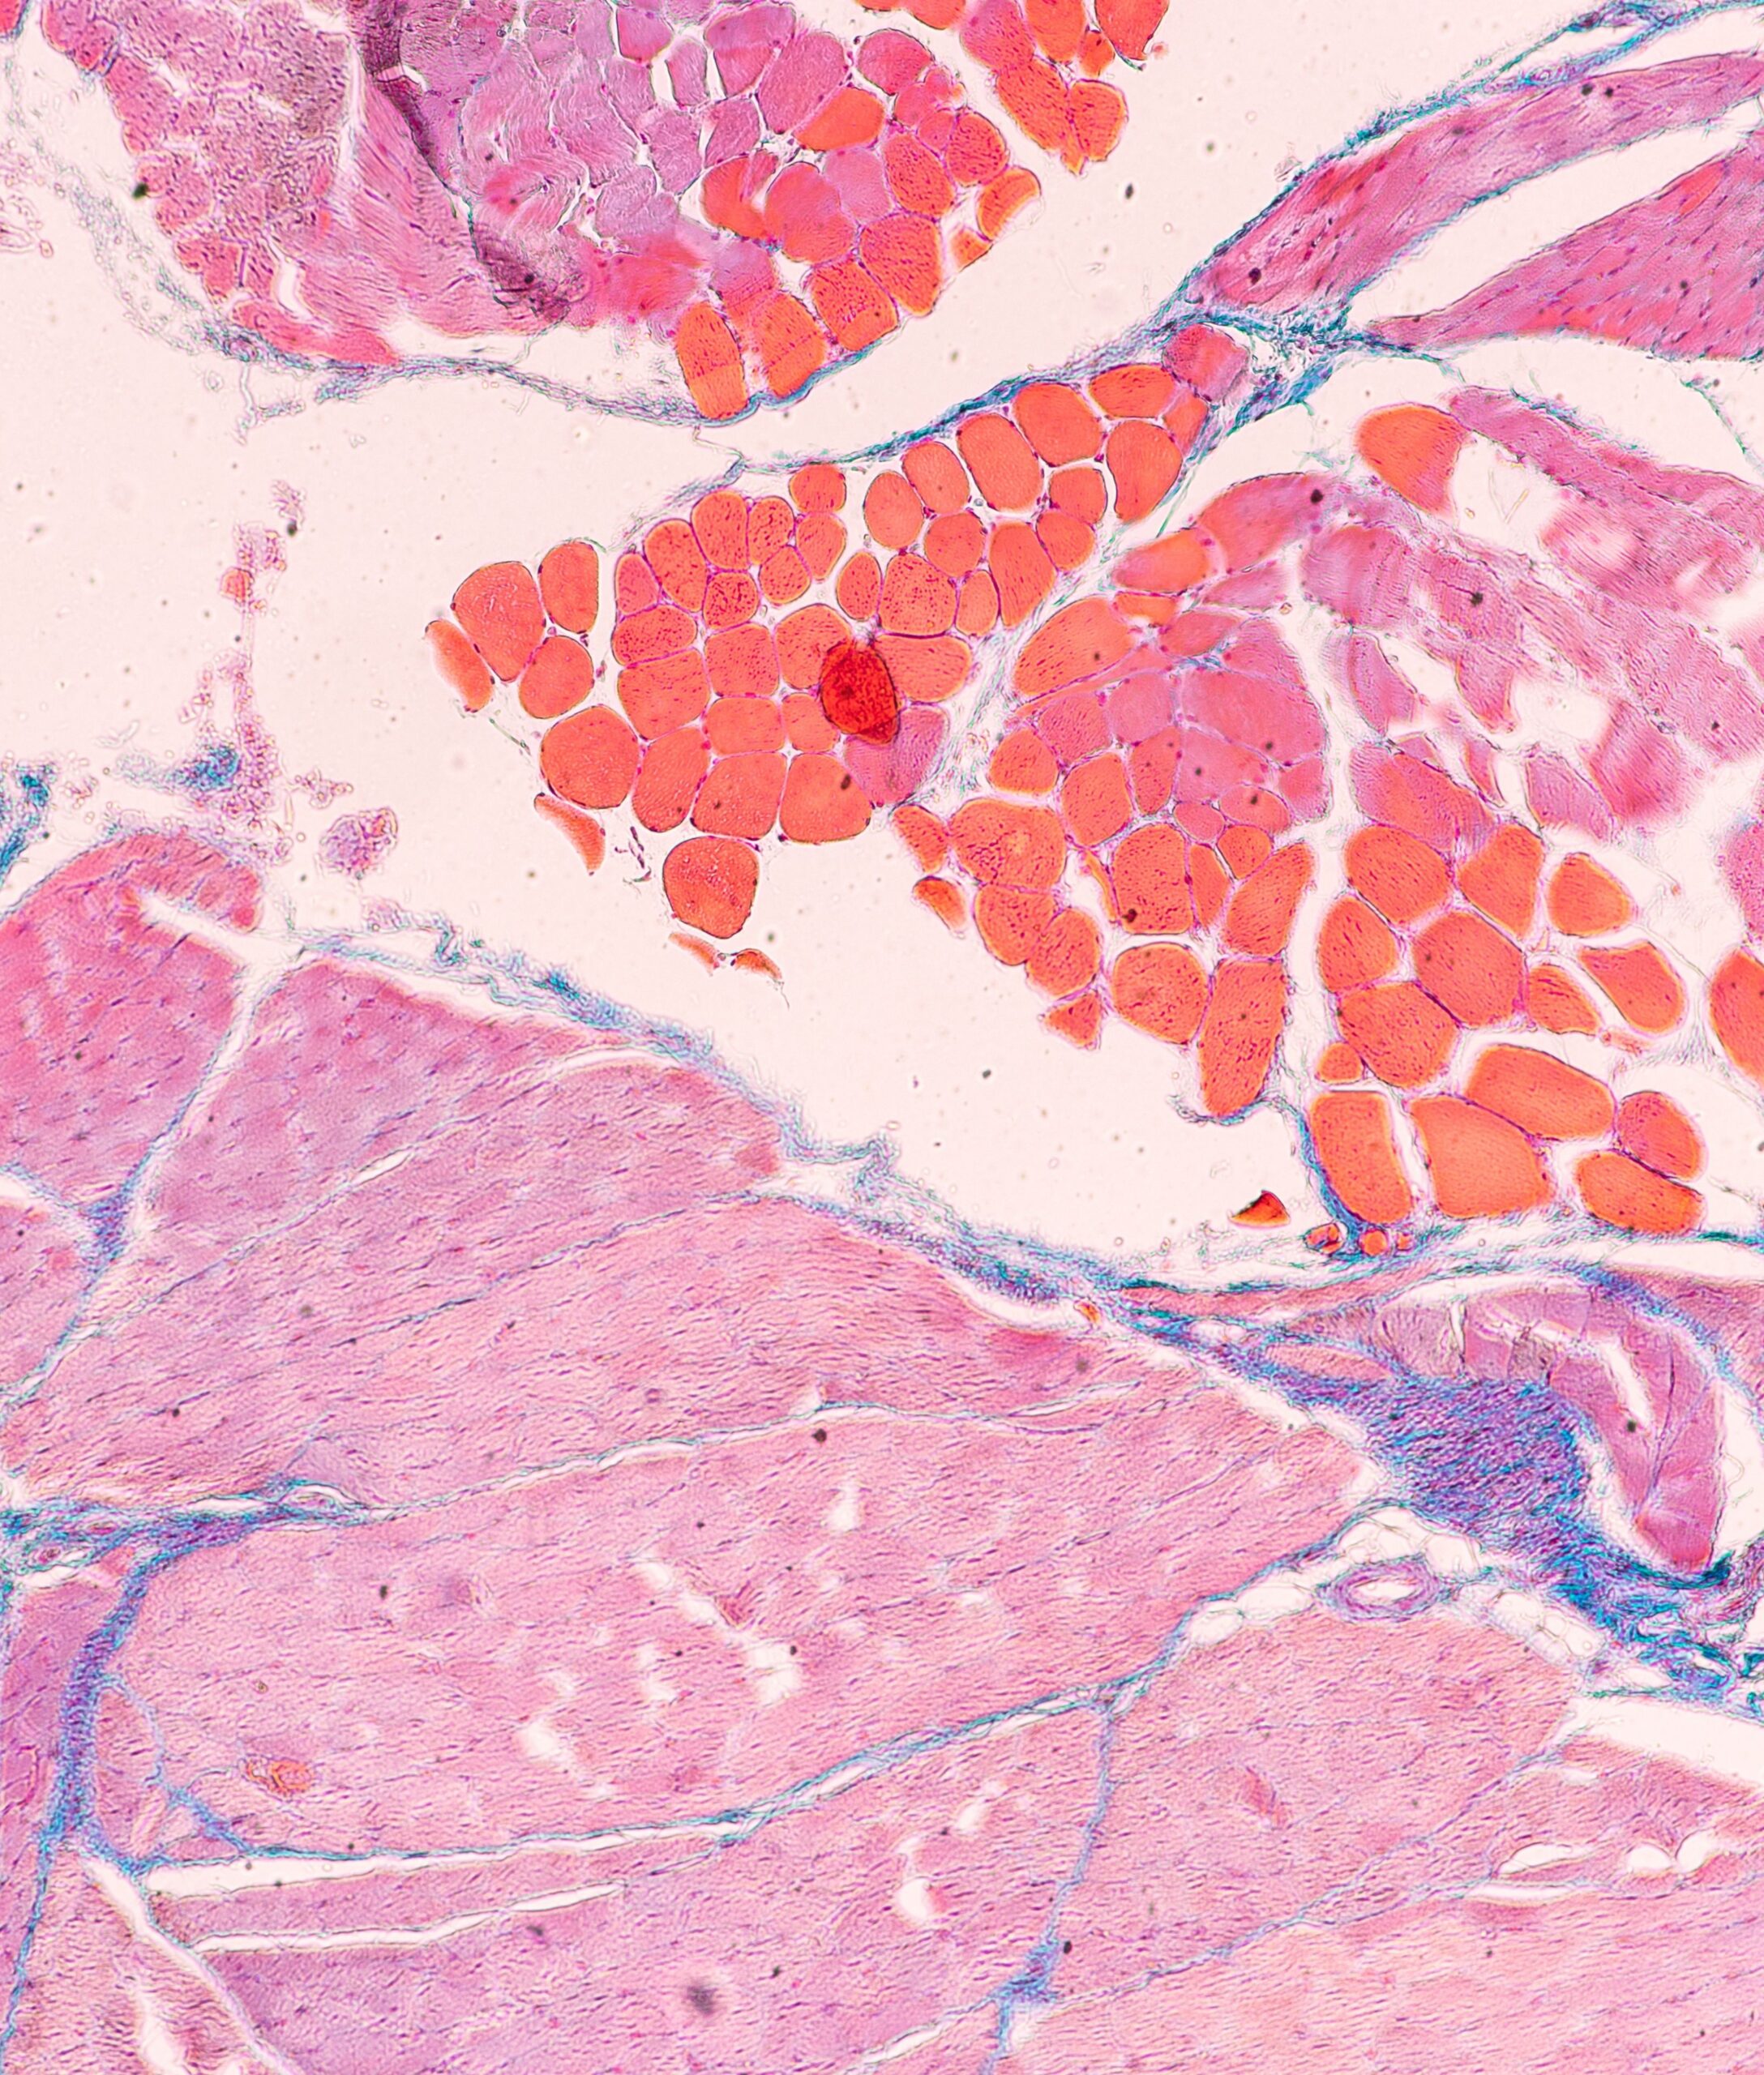

Le projet ENVie vise à développer une technologie de culture modulaire et standardisée impliquant un contrôle microfluidique des conditions environnementales, des technologies de biofabrication innovantes pour soit reconstituer une architecture d’organe et ses principales fonctions (reconstruction tissulaire, illustrée par une technologie colon-sur-puce), soit permettre l’intégration et le maintien d’un explant tissulaire (intégration tissulaire, illustrée par l’intégration d’un explant d’adénocarcinome canalaire pancréatique (PDAC) sur puce). Cette technologie garantira l’établissement, la survie et le maintien des tissus pendant des semaines, et intégrera des capacités d’imagerie et de détection 3D profondes en direct et à haute résolution pour la caractérisation et la surveillance du devenir des tissus et de leur réponse aux traitements

Le projet ENVie vise à développer un dispositif modulaire permettant la reconstruction ou l’intégration de tissu maintenu sur du long-terme et permettant sa caractérisation et l’analyse de sa réponse fonctionnelle et thérapeutique.